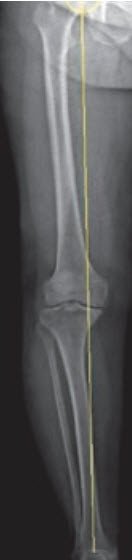

Osteoarthritis-related leg axis deviations such as knock knees or bowlegs are partially corrected during surgery.